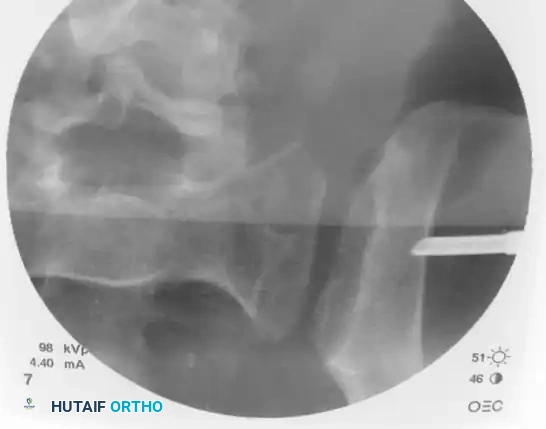

Utilizing biplanar fluoroscopic imagery—rapidly alternating between the inlet and outlet views—adjust the trajectory of the guide sleeve to safely target the center of the S1 vertebral body.

• On the Inlet View: Aim for the center of the sacral body, staying well posterior to the anterior sacral cortex and anterior to the spinal canal.

• On the Outlet View: Aim between the S1 superior endplate and the S1 neuroforamen.

Once the trajectory is perfected, advance the guidewire under power across the sacroiliac joint and into the sacral ala.

Stop advancing just before the midline. Confirm safe passage on both the inlet and outlet views.